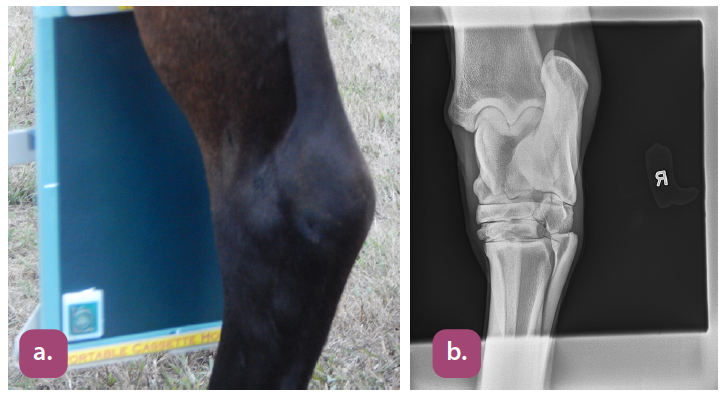

flexed lateral carpus projection

extended lateral carpus projection

dorsopalmar carpus projection

lateral tarsus projection

dorsoplantar tarsus projection